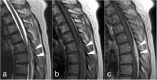

Case presentation: A 68-year-old immunocompetent woman presented with fever and sudden onset of severe back pain mimicking aortic dissection. No findings related to the pain were revealed on enhanced computed tomography or initial magnetic resonance imaging (MRI) of the spine. The patient was found to be bacteremic with P. multocida, although she had no apparent injury related to animal contact. Repeated evaluation by MRI with gadolinium-contrast established the diagnosis of spinal epidural abscess. The patient was cured by the rapid initiation of antimicrobial therapy without surgery.

Conclusions: We describe the successful treatment of an individual with a spinal epidural abscess due to P. multocida without surgery. P. multocida infections may occur as sudden presentations. Obtaining the patient history of recent animal contact is essential. Repeated MRI evaluation may be required when spinal infections are suspected. To the best of our knowledge, this is the first report which describes a case of spinal epidural abscess due to this organism.